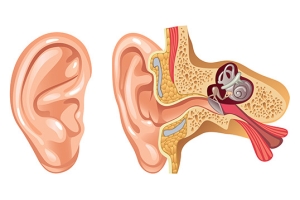

Overview

Package includes:

Days in hospital : 3 to 4 Days (For patient and one attendant)

Days in hotel : 7 Days (For patient and one attendant)

Room type in hospital : Shared

Room type in hotel : Private

Hotel category: Standard

Value added benefits of the Mastoidectomy and Tympanoplasty Including Meatoplasty:

Overview

Package includes:

Days in hospital : 2 to 3 Days (For patient and one attendant)

Days in hotel : 7 Days (For patient and one attendant)

Room type in hospital : Shared

Room type in hotel : Private

Hotel category: Standard

Value added benefits of the FESS Bilateral:

Overview

Package includes:

Days in hospital : 2 to 3 Days (For patient and one attendant)

Days in hotel : 6 Days (For patient and one attendant)

Room type in hospital : Shared

Room type in hotel : Private

Hotel category: Standard

Value added benefits of the Tympanoplasty:

Overview

Package includes:

Days in hospital : 2 to 3 Days (For patient and one attendant)

Days in hotel : 5 Days (For patient and one attendant)

Room type in hospital : Shared

Room type in hotel : Private

Hotel category: Standard

Value added benefits of the Stapedectomy: